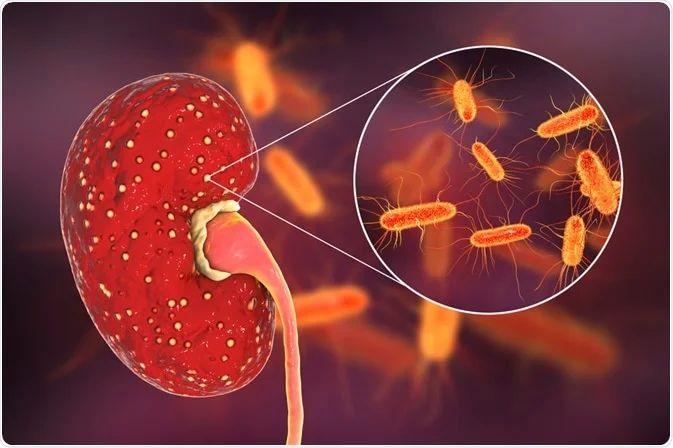

نغطي كل التخصصات الطبية

استیعاب کافة الحالات الطبیة لشمولیة التخصصات